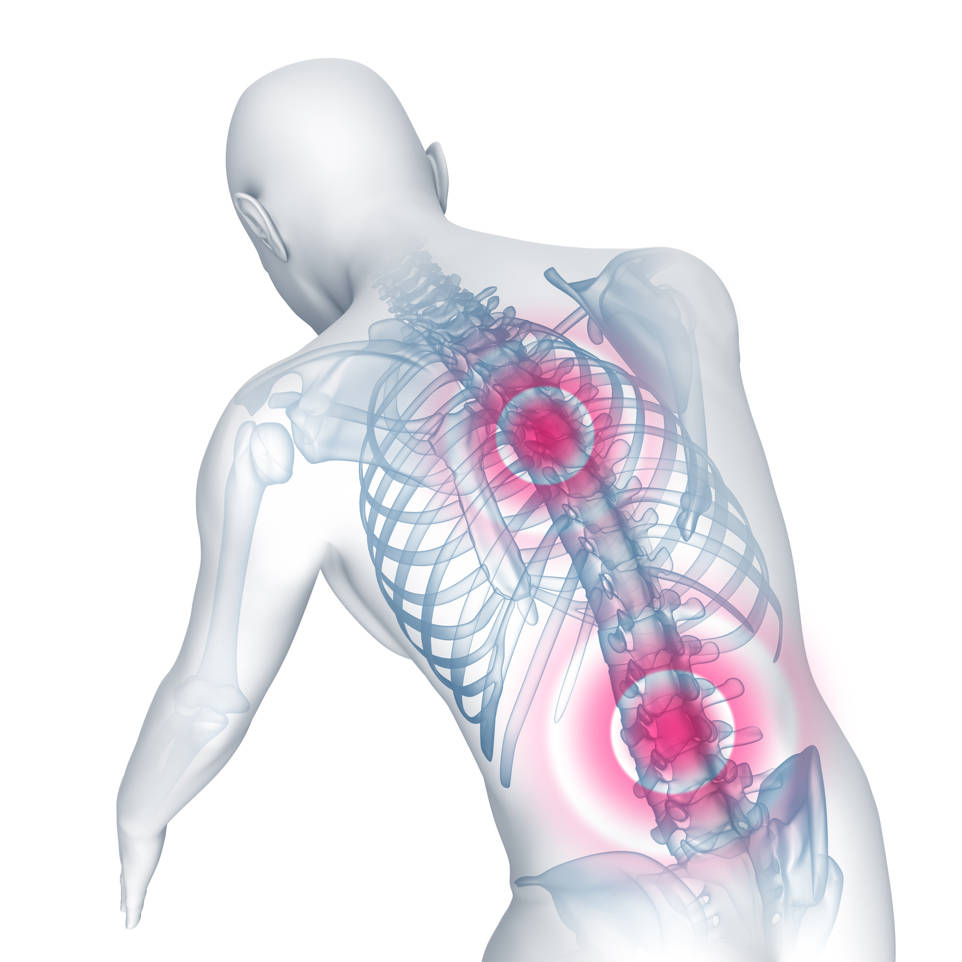

La espondilitis anquilosante (EA) es una enfermedad autoinmune que provoca la inflamación de las articulaciones, siendo la columna vertebral la más afectada.

El principal síntoma es el dolor de espalda o lumbago. En ocasiones puede producir síntomas similares a la ciática, ya que una de las articulaciones más afectada es la articulación sacroilíaca que produce un dolor irradiado por las nalgas y por la cara posterior del muslo.

Otra característica de la EA es que la inflamación no solo afecta a la espalda sino que pueden verse afectadas otras articulaciones como los tobillos, rodillas y caderas.

La rigidez es otro de los síntomas principales de la EA y quizás sea el síntomas mas invalidante ya que limita la función.